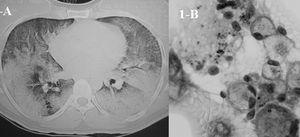

Varón transexual de 30 años, natural de Ecuador, sin hábitos tóxicos, sometido a implantes mamarios de silicona 6 meses antes, que acudió a urgencias por cuadro de 3 días de evolución consistente en disnea de comienzo brusco hasta ser de reposo, fiebre de 38,5 °C, escalofríos y sensación de muerte inminente. En la exploración destacaba temperatura de 37,3 °C, frecuencia cardíaca de 110 lat/min, frecuencia respiratoria de 30 respiraciones/min, sin cianosis, y disminución del murmullo vesicular bilateral; el resto era normal. En la radiografía de tórax se apreciaba patrón alveolar bilateral bibasal y periférico. La gasometría arterial fracción inspiratoria de oxígeno (FiO2) de 0,21 mostró pH de 7,45, presión arterial de anhídrido carbónico (PaCO2) de 35 mmHg, presión arterial de oxígeno (PaO2) de 60 mmHg, saturación arterial de oxígeno del 90% y bicarbonato de 23 mmol/l. En la analítica sanguínea destacaba una cifra de 12.500 leucocitos con fórmula normal; el hemograma, la bioquímica y la coagulación eran normales. Se diagnosticó al paciente de neumonía grave adquirida en la comunidad e insuficiencia respiratoria aguda, y ante la sospecha de infección por el virus de la inmunodeficiencia humana se inició desde urgencias tratamiento con cefotaxima, claritromicina y cotrimoxazol. Con posterioridad refirió que el cuadro había comenzado inmediatamente después de la inyección de 125 ml de silicona líquida en la región trocantérea de los muslos. Además, refería que 4 años antes había presentado un cuadro similar en su país de origen. Se realizó una fibrobroncoscopia en la que no se apreciaron lesiones, así como catéter telescopado en el lóbulo inferior derecho y lavado broncoalveolar (BAL), pero no pudo realizarse biopsia transbronquial debido a que la saturación arterial de oxígeno era del 90% con oxígeno al 50%. En las 12 h siguientes el paciente presentó empeoramiento clínico y gasométrico (FiO2 de 0,5): pH de 7,43, (PaCO2) de 36,1 mmHg, PaO2 de 65 mmHg, bicarbonato de 23 mmol/l y PaO2/FiO2 de 121. En la radiografía de tórax se apreció progresión del patrón alveolar bilateral, por lo que ingresó en la Unidad de Cuidados Intensivos. La tomografía computarizada de tórax mostró patrón alveolar panlobular con broncograma aéreo (fig. 1A). Todas las muestras obtenidas fueron negativas. El análisis del BAL mostró 625 células/ml con un 83% de macrófagos, un 12% de neutrófilos, un 3% de linfocitos y un 2% de eosinófilos. La tinción del BAL mostró inclusiones micro y macrovacuoladas en los macrófagos indicativas de partículas de silicona (fig. 1B), con lo que se confirmó el diagnóstico de neumonitis aguda por silicona (NS) con síndrome de distrés respiratorio. Tras el ingreso en la Unidad de Cuidados Intensivos, se retiraron los antibióticos y se inició tratamiento con 20 mg de metilprednisolona por vía intravenosa cada 8 h y oxigenoterapia a alto flujo sin soporte ventilatorio, con el que el paciente experimentó una gradual mejoría gasométrica. Los hemocultivos, la serología del virus de la inmunodeficiencia humana, el antígeno de Legionella y de neumococo en orina y serología respiratoria fueron negativos. En el momento del alta (día 10 de ingreso) la tomografía computarizada de tórax y la exploración funcional eran normales.

Fig. 1. Corte de la tomografía axial computarizada de tórax realizada durante el ingreso en la Unidad de Cuidados Intensivos, donde se observa el patrón alveolar panlobular con broncograma aéreo (A), y muestra de lavado broncoalveolar que muestra inclusiones micromacrovacuoladas en los macrófagos alveolares (B).

En 1975 se describe el primer caso de NS1 y posteriormente se publican varias comunicaciones de edema pulmonar, distrés o derrame pleural bilateral relacionadas con inyecciones subcutáneas de silicona en mamas, región malar, glúteos o región trocantérea. En 1983 Charstre et al2 publican una serie de 5 pacientes con lesión pulmonar y demuestran que la sustancia obtenida del sobrenadante del BAL era la misma que se había utilizado para las inyecciones y, además, que las inclusiones globulares en el citoplasma de los macrófagos alveolares correspondían a partículas de silicona. Se han descrito 2 formas de NS. La aguda2-6 cursa, como en nuestro caso, con disnea de comienzo brusco, taquicardia, taquipnea, fiebre elevada y, en ocasiones, dolor torácico o hemoptisis. Suele aparecer inmediatamente después de la inyección o en un intervalo de 24 h. El volumen de silicona inyectado oscila entre 100 y 250 ml. Afecta a personas sanas y debe descartarse la presencia de infecciones, fármacos o drogas como causantes del cuadro. Tal como sucedió en nuestro paciente, cursa con hipoxemia moderada o grave y en ocasiones con insuficiencia respiratoria aguda. Radiológicamente se caracteriza por patrón alveolar bilateral o infiltrados intersticiales bilaterales con áreas parcheadas de consolidación. El tratamiento suele ser conservador, con reposo y oxigenoterapia a altos flujos, si bien en algunos casos es necesario el soporte ventilatorio. Existen discrepancias sobre el uso de esteroides, ya que no existe una evidencia clara de que la evolución sea mejor con este tratamiento. En general, el cuadro se resuelve sin secuelas, aunque se ha descrito un caso de evolución a fibrosis pulmonar4. Aunque el BAL puede mostrar aumento de la celularidad a expensas de macrófagos alveolares, neutrófilos y eosinófilos, el hallazgo de inclusiones en los macrófagos con aspecto globular es característico y diagnóstico de la NS. La espectrofotometría y la microscopia electrónica confirman su naturaleza2,3. La presencia de dichos hallazgos podría obviar la realización de biopsia transbronquial o biopsia abierta4,5. En este sentido, se han descrito 4 patrones histológicos6: la mera presencia de émbolos de silicona; congestión y hemorragia; neumonitis aguda, y lesión alveolar difusa. Se ha descrito también la forma latente3, que acontece entre 6 y 13 meses después de la inyección y afecta a quienes presentaron edema e hinchazón local, con síntomas respiratorios leves e hipoxemia. En la patogenia de la NS se implica un proceso de embolización al pulmón tras la difusión de la silicona al sistema circulatorio, favorecido por una elevada presión local tisular, masajes, migración o inyección directa. La presencia ocasional de hemorragia alveolar y exantema petequial apunta a este mecanismo, semejante a la embolia grasa. Otra hipótesis plantea que se trataría de un proceso inflamatorio mediado por células; a favor de esta teoría estarían las inyecciones previas y la linfocitosis en el BAL3.